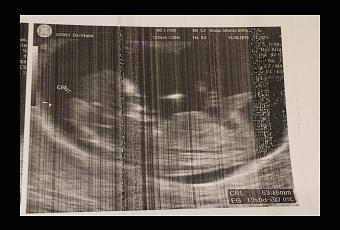

Hoy no tengo muchas cosas para decir, pero todas importantes. Sigo sintiéndome muy cansada pero muy contenta. Ya se me nota la barriga y he aumentado dos kilos. Me han hecho la primera ecografía de la seguridad social y ha salido todo muy bien, he visto a mi peque estirándose, moviéndose, me han mostrado sus manos y pies, han realizado el tiple screening, (en donde además de ver el latido del corazón y hacer las medidas regladas; cabeza, abdomen y fémur para establecer la edad gestacional, está ecografía permite diagnosticar grandes malformaciones y determinar el grosor del pliegue nucal). Ha salido riesgo bajo, así que todo fenomenal.

El bebé ya mide 6 cm y todo va acorde con la edad gestacional.

12 semanas de embarazo